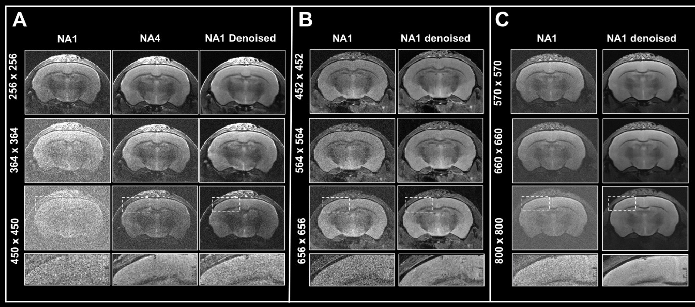

Figure 6. Boosting resolution. Ex vivo T2-weighted TurboRARE data of a fixed mouse head acquired at A) 3 Tesla, B) 7 Tesla, and C) 9.4 Tesla. All images were acquired with 0.8 mm (A) and 0.7 mm (B, C) slice thickness and with a field-of-view of 20 x 20 mm2 and the given matrix size using either no averaging or acquiring 4 averages. Images were reconstructed with no denoising (NA1 and NA4), or after denoising (NA1 Denoised) using a network Large, applying a pre-denoising level of 50% and denoising level of 70%. Image Credit: Bruker BioSpin Group

In Fig. 6, axial T2-weighted TurboRARE images of a fixed mouse head obtained at various field strengths are contrasted. Images were obtained via a fixed field-of-view of 20 x 20 mm2, with 0.8 mm (3 Tesla) and 0.7 mm (7 and 9.4 Tesla) thick slices and with diverse matrix sizes to generate images with various spatial resolutions.

Of particular note, the matrix sizes were made larger by up to a factor of 1.8, 2.6, and 3.1 (vs a matrix size of 256 of the reference protocols) for images obtained at 3, 7, and 9.4 Tesla, respectively. These resolution increases lead to a concomitant loss in SNR for each image. Loss in SNR can be made up for by utilizing averaging and thus additional data was obtained with four averages.

Comparing non-denoised averaged images with single averaged images showed that denoising reduces increased image noise at elevated resolutions and results in images of similar quality to those obtained through averaging.

Improvements in image quality by denoising are more significant with data obtained at 3 Tesla, where heightening the resolution generates images that are more difficult to understand, compared to data obtained at 7 and 9.4 Tesla, where SNR is innately higher.

In any case, images obtained at 7 and 9.4 Tesla are significantly helped by denoising during reconstruction, as the intrinsically elevated SNR of these images can be used for choosing smaller voxel dimensions. Thus, denoising enables researchers to choose higher resolutions within a given unit of time, stemming from a reduced need for averaging. This can also be practical when averaging might be undesirable or impractical.